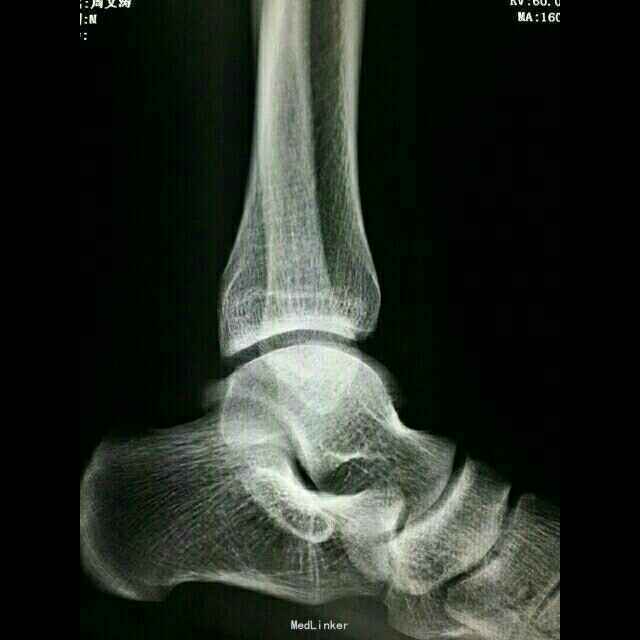

主诉:左踝关节扭伤后肿痛5天。 病史:患者男,20岁,从约1.5米高处跳下后致左踝肿痛,活动受限,当时未做特殊处理。次日感症状持续存在,且出现局部淤青,予以冰敷,云南白药气雾剂等处理,症状无明显缓解,遂来本院就诊。

查体:左足背皮下淤血,外踝及足背肿胀明显,局部压痛,活动受限,未及骨擦感。 辅助检查:左距骨囊性变并死骨形成,考虑距骨无菌性坏死可能。CT及MRI检查支持该诊断。

诊断: 1.左距骨无菌性坏死; 2.左踝急性创伤性滑膜炎。 治疗: 1.加强休息,患肢制动; 2.活血化瘀,对症支持治疗; 3.局部理疗。